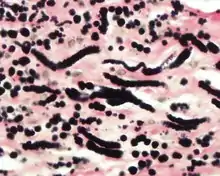

By microscopie view, there is an admixture of heavy dense bands of collagenous tissue dissected by fat and abnormal elastic fibers. The elastic fibers are often quite large and are easily identified. The elastic fibers are coarse, thick, and darkly eosinophilic, often fragmented into globules, creating a "string of pearls" or "pipe cleaner" appearance. Because of degeneration, the elastic fibers will appear as globules with a serrated or "prickled" edge.[4]

The elastic fibers will be highlighted by a Weigert or von Gieson elastic stains.[8]